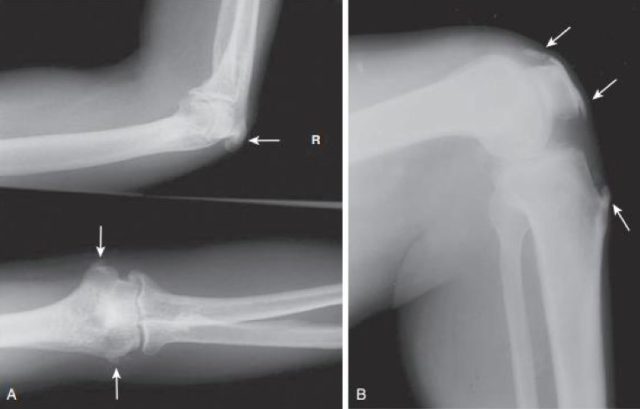

图 2 A 和 B 所示:髌骨周围、鹰嘴和肱骨上髁(箭头所指)骨化的肌腱端